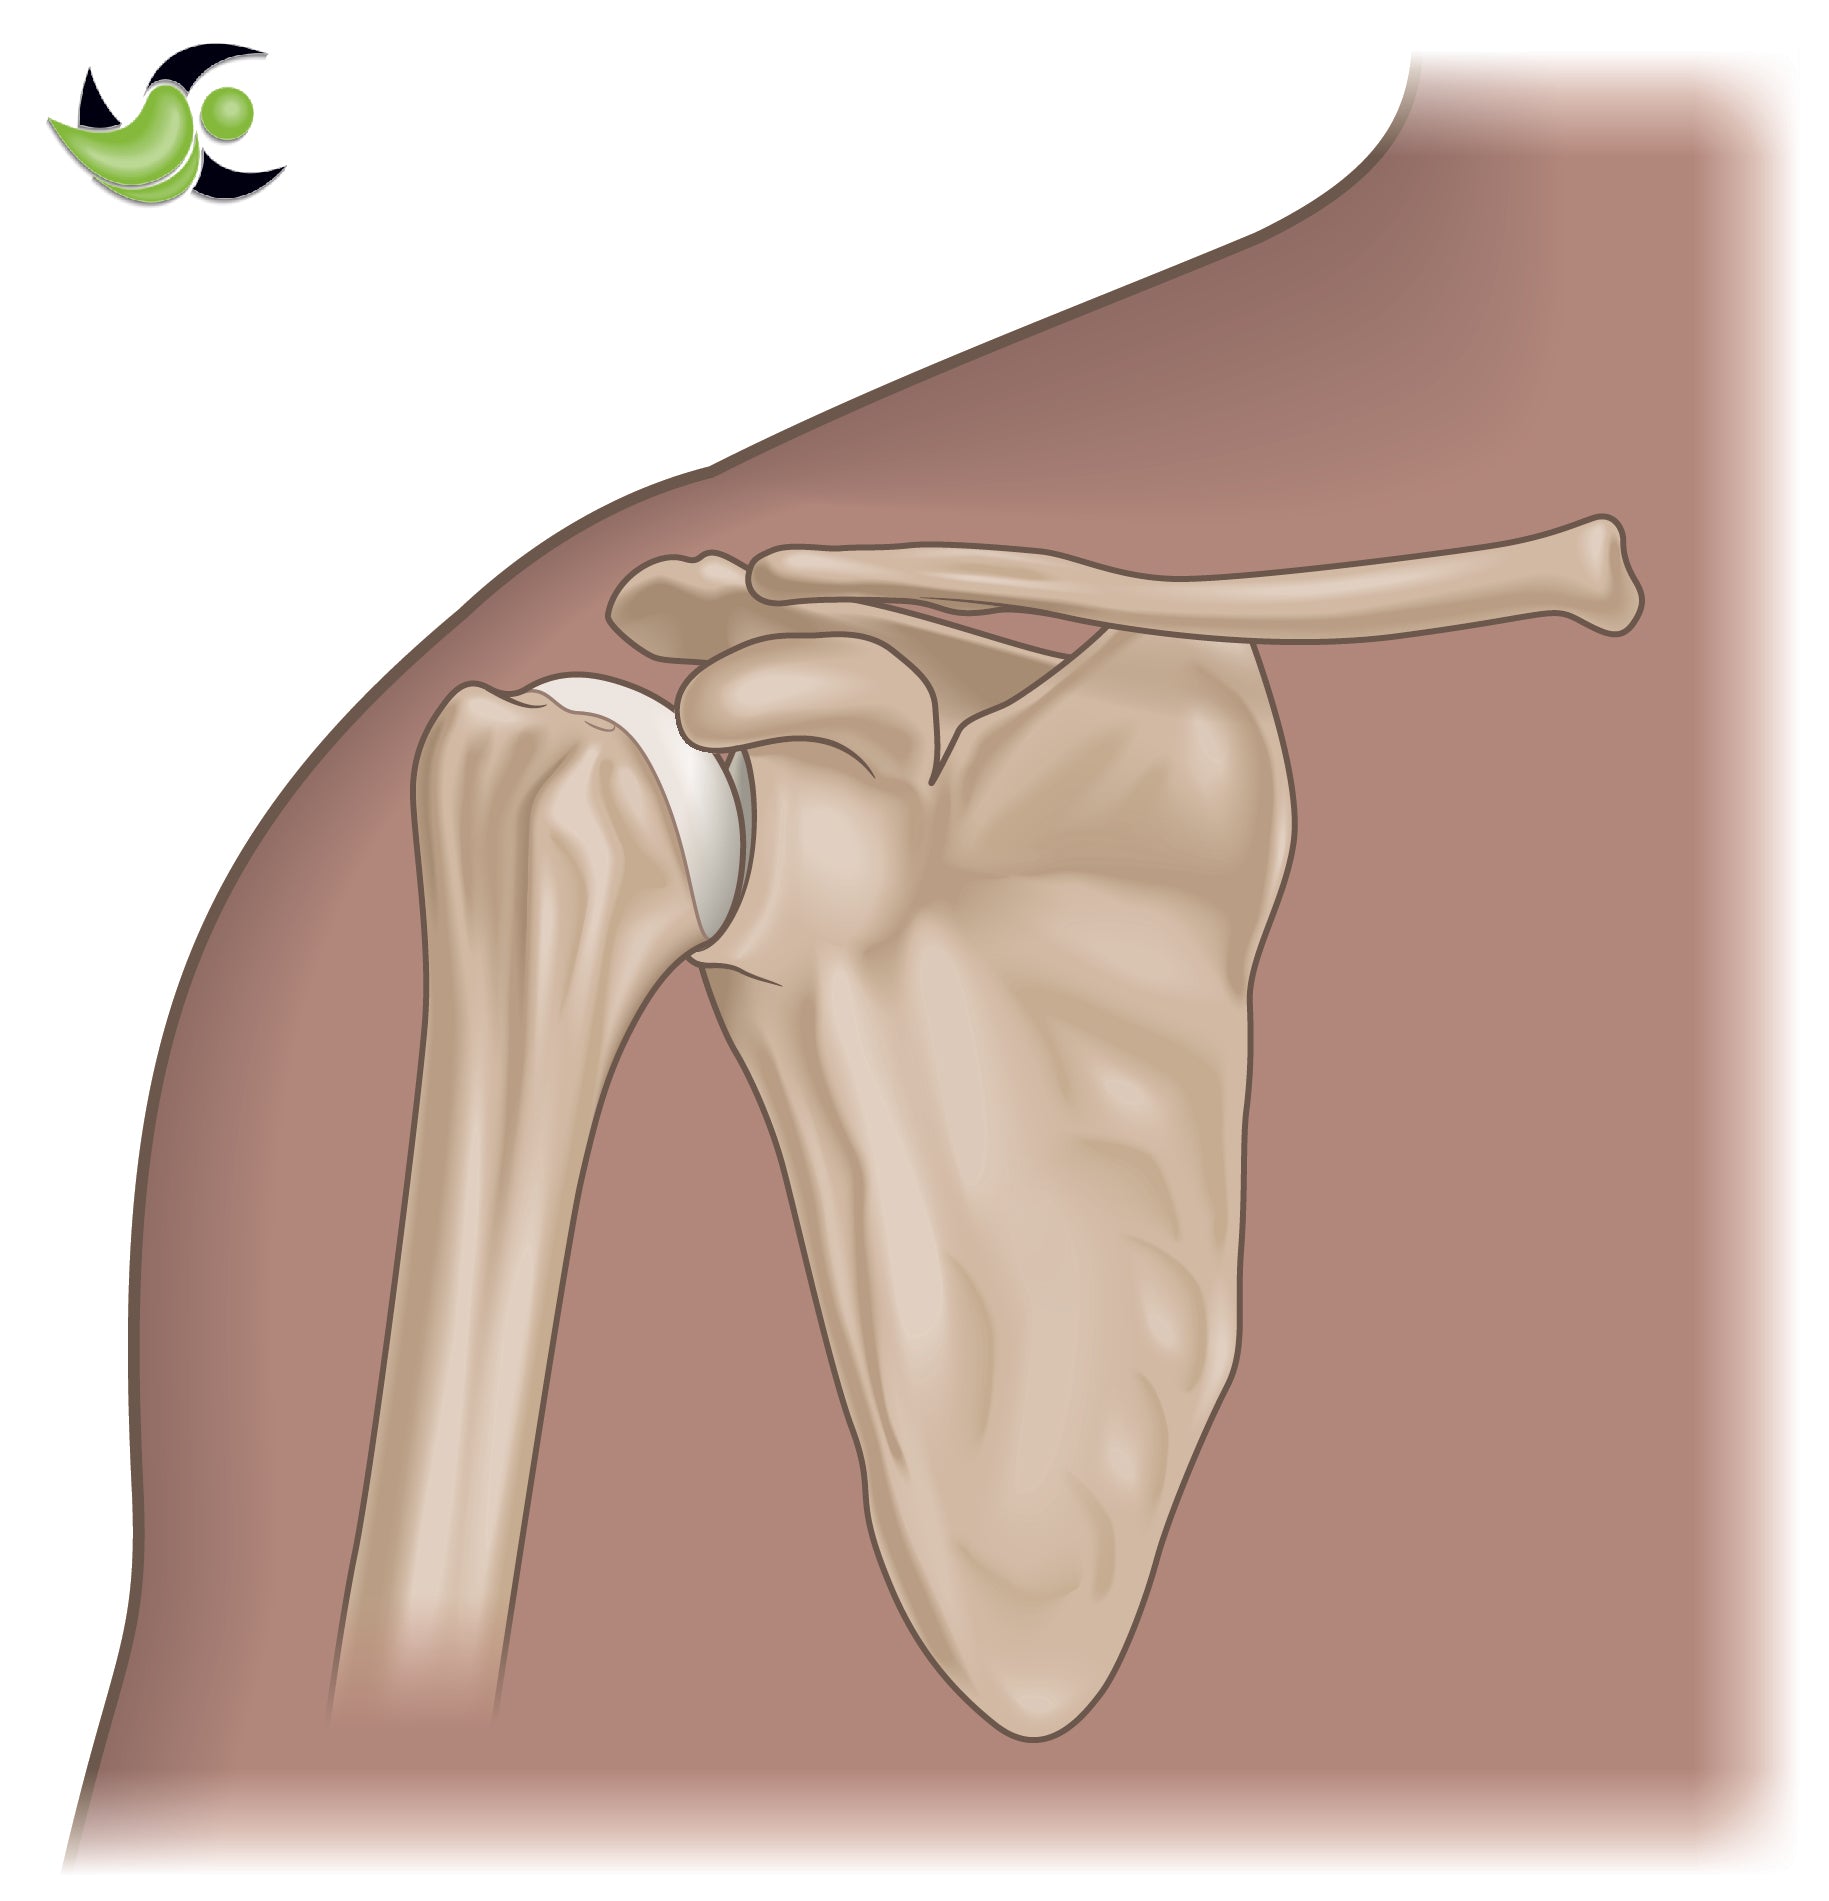

Fractures of the shoulder most commonly include either clavicle (collarbone) fractures or proximal humerus (ball) fractures. Less commonly involved fractures of the shoulder include the glenoid (socket) and the scapula (shoulder blade). Fractures are broken bones and can range in severity from a mild crack to a large break including multiple broken pieces. They are most commonly caused by accidents such as: motor vehicle accidents, a fall, or a direct blow to the area.

The AC joint is where the collar bone meets the acromion of the shoulder blade. The joint is held together by a series of ligaments: The acromioclavicular ligament, the coracoclavicular ligaments (coronoid and trapezoid ligaments), and the coracoacromial ligament. There are different types of AC joint separations. Depending on the type of tear and which ligaments are torn, you may or may not need surgery.